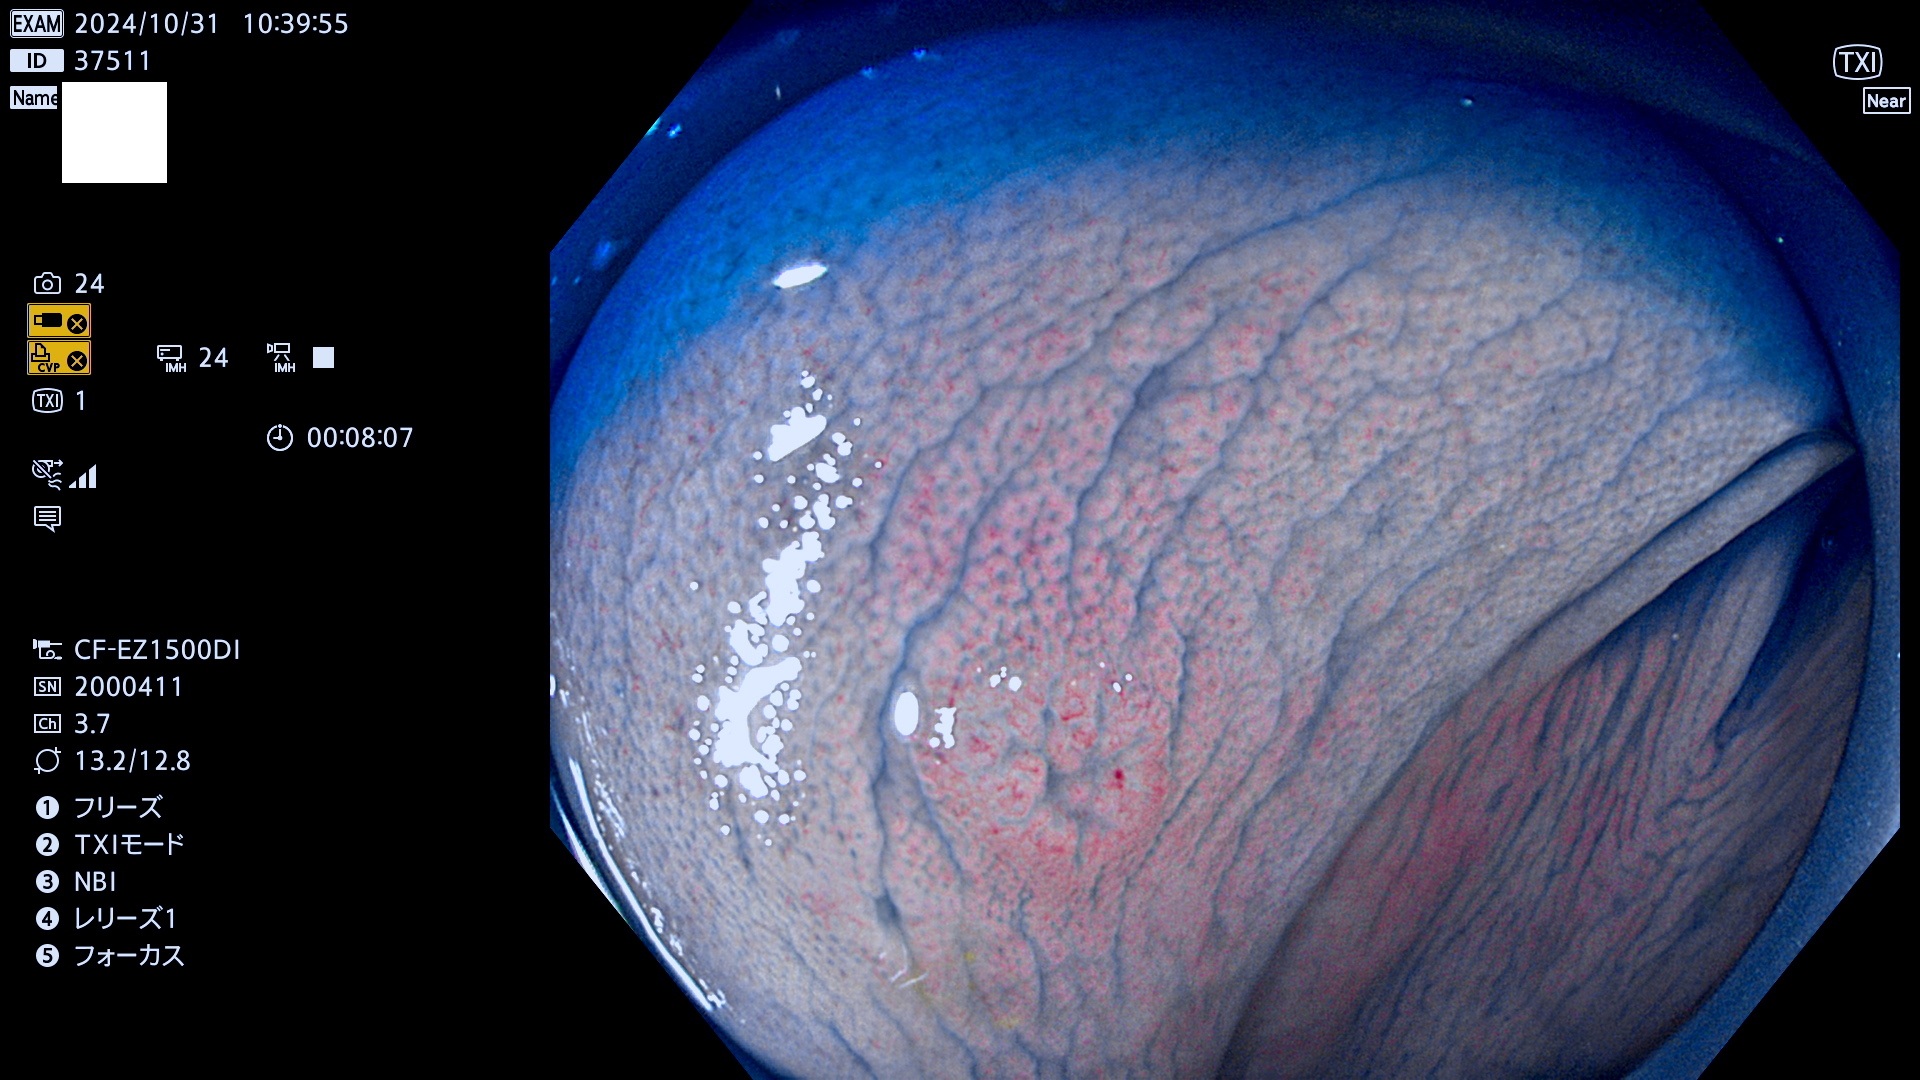

完全に平坦な物をUb、陥凹している物をUcと呼びます。最も発見が難しく危険な病変です。

毎週の検査(木・金・土・日)に発見されたUb、Uc型・腺腫を、その週の日曜の夜にUPし1週間、提示します。

抽出の対象期間 2024年10月31日〜11月3日の4日間(48件の検査)7件 (7/48=15%)